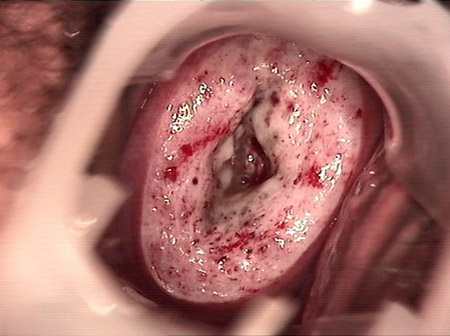

CIN 2-3

CIN 2-3 修復(fù)后